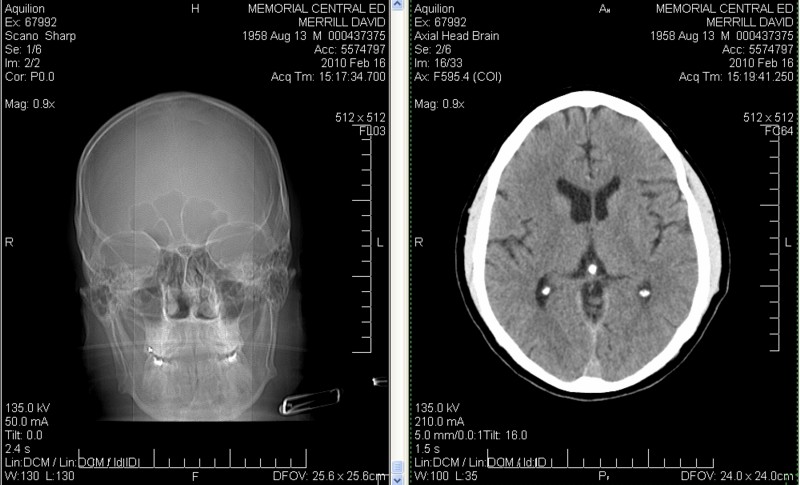

U - Inside David Merrill's Head